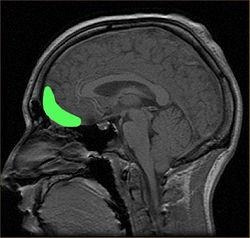

다마지오는 감정을 나타내는 것에 문제를 가진 이들의 뇌 영역을 연구했습니다. 그리고 많은 영역이 감정적 활동에 영향을 미친다는 것을 관찰합니다. 다마지오는 특히 중요해 보이는 한 곳을 지목합니다. 안와전두엽 orbitofrontal cortex. 라틴어 orbit는 안와, 눈구멍을 뜻합니다. 즉 안구 바로 뒤에 있는 전전두엽의 한 부분을 말합니다. 다마지오는 바로 이 영역이 손상되었을 때 결정장애가 발생한다고 이야기합니다.

『How We Decide, 우리는 어떻게 결정하는가』의 저자 조나 레러(Jonah Lehrer)는 안와전두엽이 뇌 속의 감정을 의식적인 사고와 연결하는 부위라고 이야기합니다.